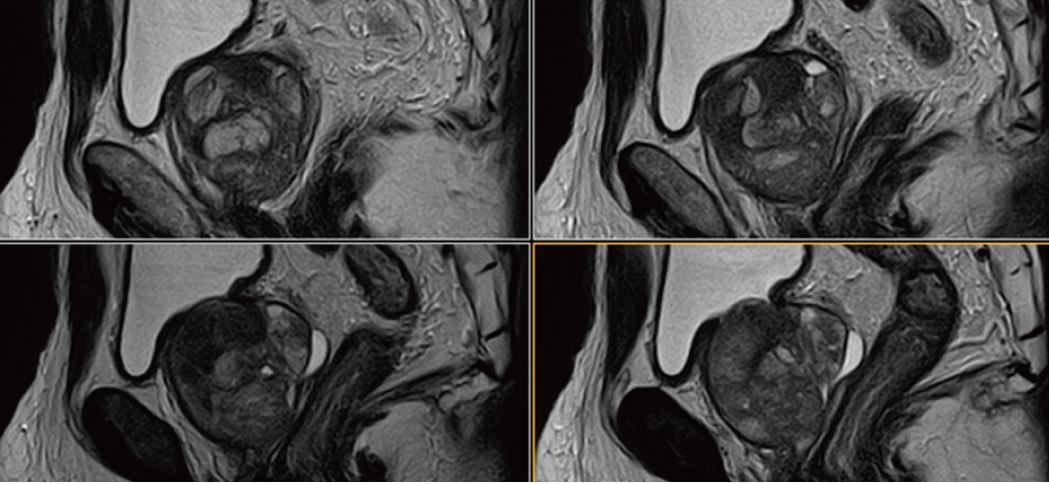

Рис. 1.  Сагітальне, Т2-зважене зображення.

Рис. 5. Сагітальне,  Т2-зважене зображення.

Рис. 9. Сагітальне, Т2-зважене зображення.

Рис. 13. Сагітальне, Т2-зважене зображення.